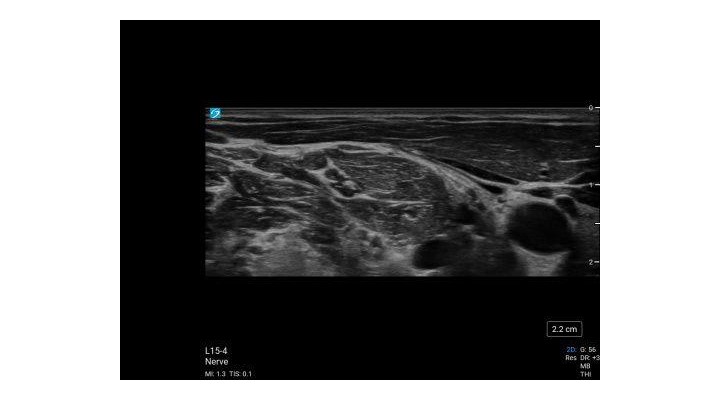

- The ultrasound transducer is placed transverse and superior to the clavicle to identify the subclavian artery and the brachial plexus located lateral and superficial to the artery.

- The ultrasound transducer is moved superiorly following the brachial plexus to the level of the cricoid cartilage.

- The C5, C6 and C7 nerve roots can be easily identified by ultrasound at this level.

L15-4, L19-5, L12-3